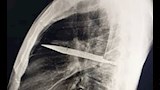

وأظهرت الفحوص السريرية أن الجزء الأيمن من صدره لا يتمدد بالكامل أثناء التنفس، فيما كشفت الأشعة السينية وجود شفرة سكين كبيرة عالقة في تجويف الصدر، ممتدة من الظهر إلى مقدمة القفص الصدري، ومحاطة بطبقات من القيح والأنسجة الميتة.

وأجرى الأطباء عملية بضع الصدر لإزالة الشفرة وتفريغ القيح وغسل التجويف بمحلول ملحي، ثم وضع أنبوب تصريف وخياطة الجرح، إذ تلقى المريض مضادات حيوية واسعة الطيف لمدة سبعة أيام، وتمت متابعة حالته على مدى أسابيع للتأكد من عدم حدوث مضاعفات.